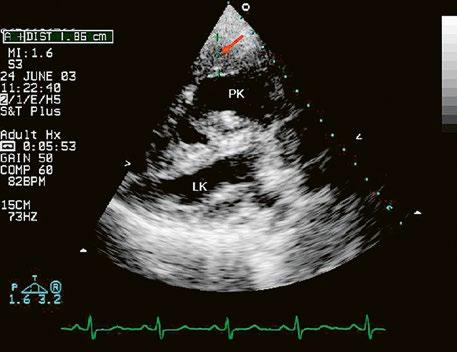

Poslechový nález systolického šelestu nad plicnicí s fixním rozštěpem 2. ozvy je nenápadný. Echokardiograficky je patrná dilatovaná a objemově přetížená pravá komora s paradoxním pohybem septa (Obr. 45.9), zkratový tok může být vidět i transtorakálně (TTE) (Obr. 45.10, Video 45.3, Video 45.7), ale suverénní diagnostickou metodou je jícnová echokardiografie (TEE), případně s 3DE zobrazením (Obr. 45.1, Obr. 45.2,

Obr. 45.10 TTE, čtyřdutinová apikální projekce s levo pravým zkratem na úrovni síní (šipka) při defektu septa síní typu secundum PK – pravá komora, LK – levá komora, LS – levá síň, PS – pravá síň